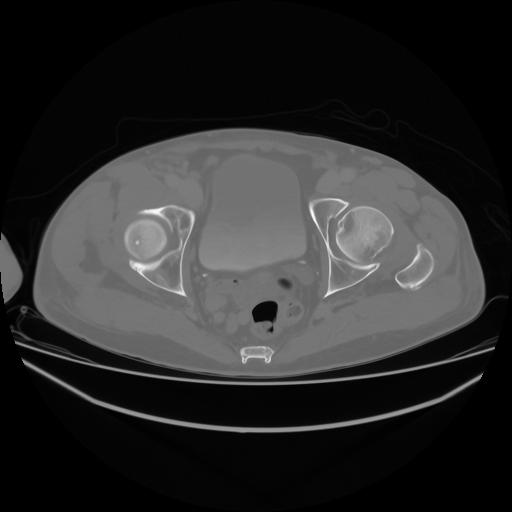

4 CUERPO,CE,Axial,3.0,CUERPO,,